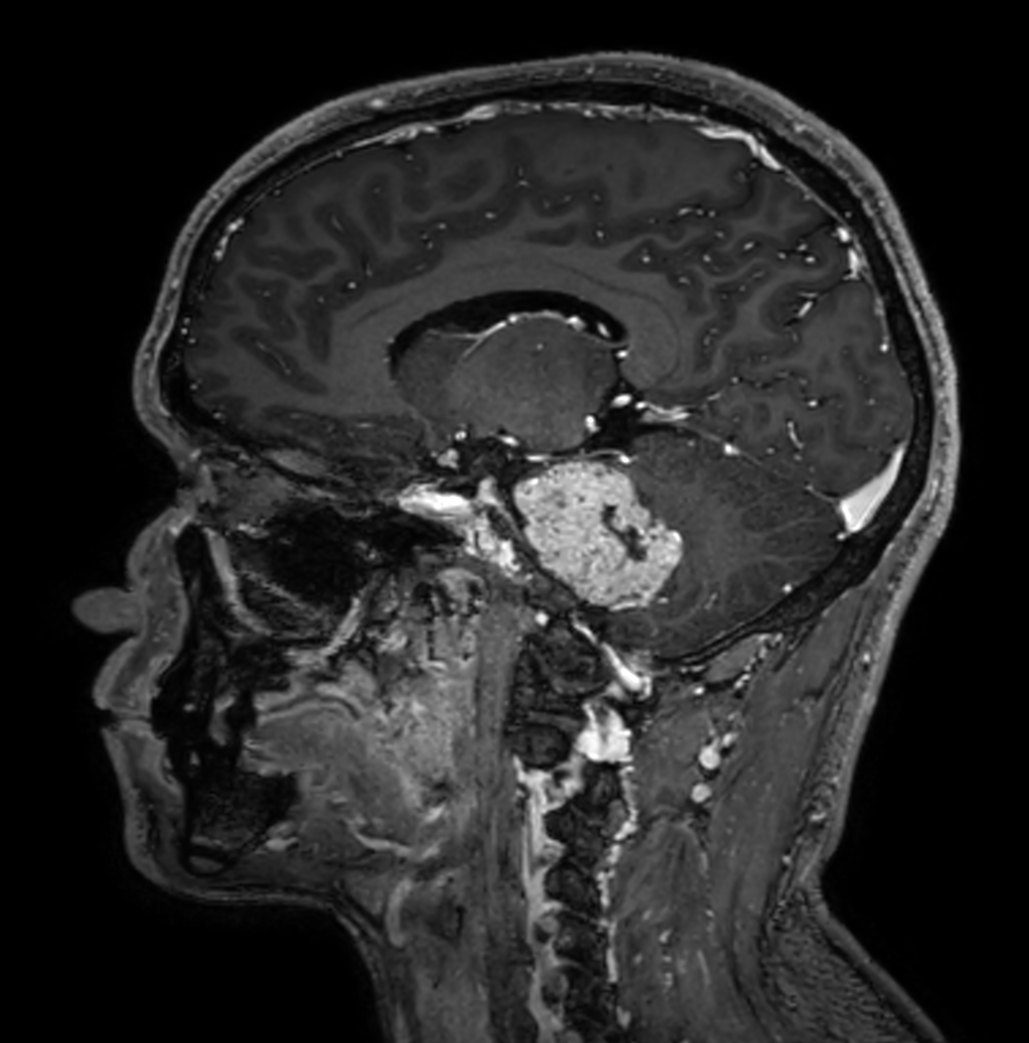

Patient with a brain (IAC) lesion. Compressed SENSE is used to shorten the scan time of the high resolution clinical scans, whilst MultiBand SENSE is used to reduce the scan time of the functional (DTI) scan.

Sagittal 3D T1w TFE BrainVIEW with gado